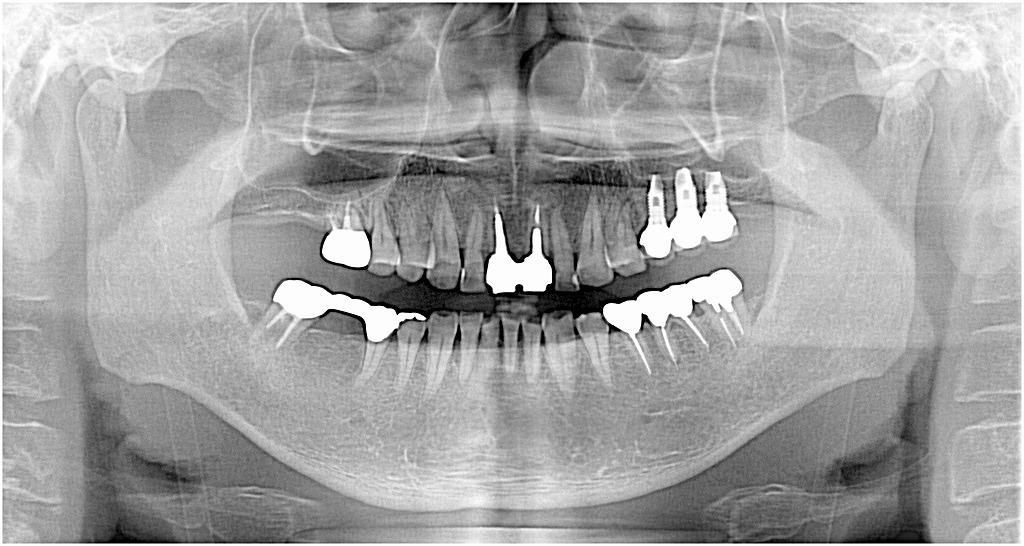

パノラマにて

治療後はこのようなパノラマ像になります

臼歯部の安定がうかがえます

すべて10㎜以上のインプラントとなりました